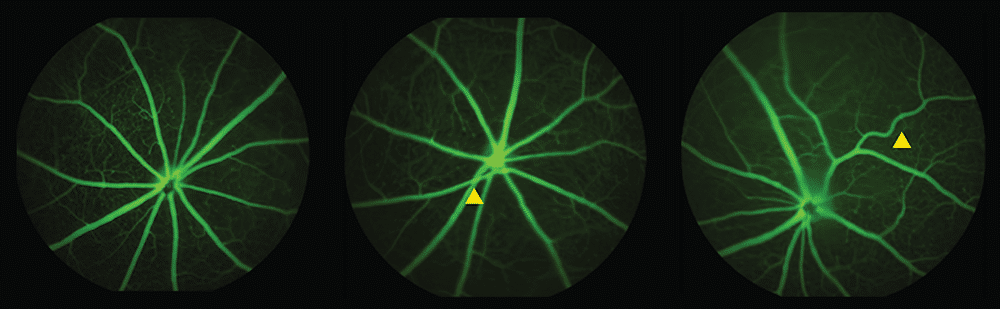

Using standard ophthalmology equipment similar to what eye doctors use in clinics, researchers photographed retinal blood vessels in mice at 6 and 12 months of age. Female mice with the variant showed the most pronounced changes.

The researchers observed twisted vessels and instances where arteries pressed down on veins, narrowing blood flow. Both abnormalities are warning signs doctors already look for when assessing stroke and cardiovascular disease risk in human patients. Arteries in affected mice became narrower while veins grew wider, suggesting the vascular system was struggling with altered blood pressure.

These specific abnormalities appeared at 6 months, while broader loss of small blood vessels didn’t show up until 12 months. The timing matters because twisted vessels and arterial-venous crossings might serve as earlier markers than overall vessel density changes.